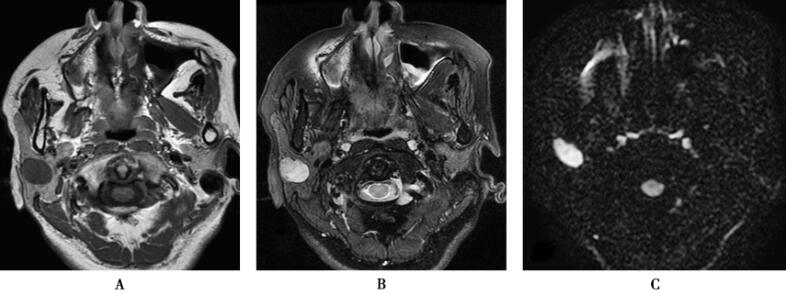

应用3.0T超导型MRI扫描仪(HDx,GE),8通道头线圈,获取SE体轴横断T1WI(TR/TE=600ms/8.68ms),3mm层厚,1mm间隔,512×512矩阵,200mm视野,FSE加脂肪抑制横断和冠状位T2WI[TR/TE=(3180~6000ms)/(44~88ms)],3mm层厚,1mm间隔,512×512矩阵,200mm视野。DWI:应用多b值成像,TR/TE=6000ms/109.9ms,3mm层厚,1mm间隔,512×512矩阵,200mm视野。应用钆喷酸葡胺(剂量0.1mmol/kg体重),以2.5ml/s流率注射,进行动态增强扫描,并作TIC曲线,获取横断位和冠状位T1WI扫描(图1)。

图1右腮腺混合瘤

1.右侧腮腺多形性腺瘤右侧腮腺浅叶上部见椭圆形病灶,边界清晰,见浅分叶,病灶内部信号欠均匀,T1WI呈稍低信号,T2WI呈高信号,信号不均匀,DWI呈高信号,增强扫描病灶延迟性强化,强化欠均匀,TIC曲线呈持续强化型。